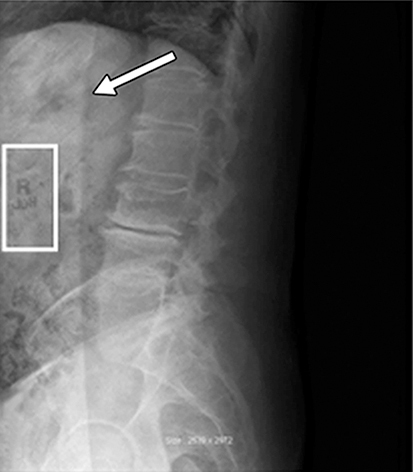

Image lag can also be corrected with the detector’s software using the dark noise or offset correction. Offset correction determines the amount of signal inherent in the detector. If an offset correction is performed prior to residual signal leaving the pixels, that information will be stored as inherent and could cause a negative image of the residual signal. Always follow the equipment manufacturer’s guidelines when performing any detector calibrations. For example, in Fig. 5.10 an offset correction was performed after an examination was done with a right-side marker in an area of unattenuated radiation. Residual signal remained in that area and a subsequent offset correction was performed. The R is now viewed inversely because that signal created a mask during the offset correction. In Fig. 5.10 it is clear that the signal is still very strong and this image was taken 10 minutes after the initial exposure.